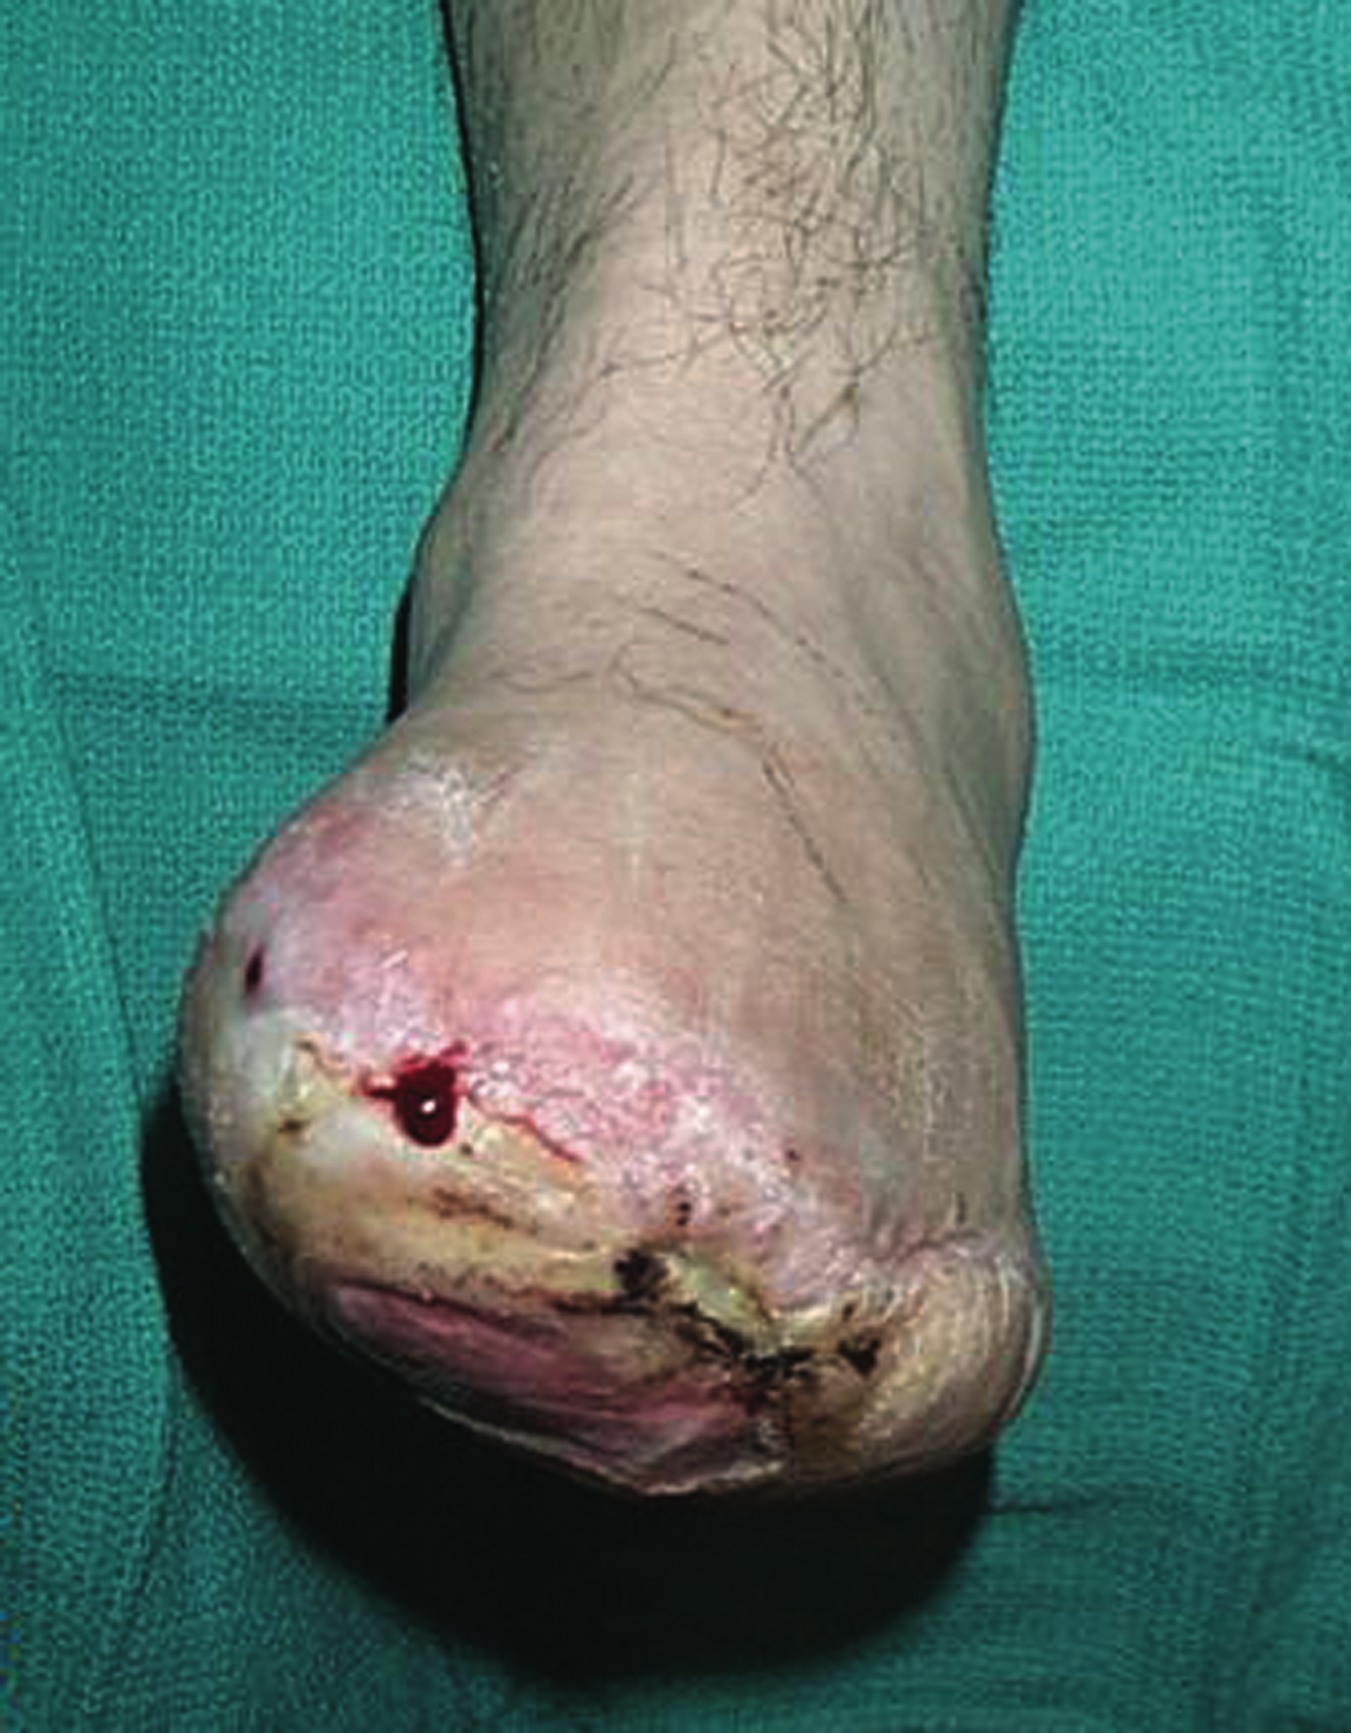

Such border conflicts are made possible by the lack of uniformity in the scope of podiatric practice from state to state. This, in turn, affects any number of issues from the education and training of podiatry residents to insurance regulations and billing once those residents graduate and start practicing. However, the ultimate losers might just be the patients who depend on DPMs for their foot care. Excessively limiting scope-of-practice laws drive a podiatrist like Michelle Butterworth, DPM, up the proverbial wall. She is the President of the South Carolina Podiatric Medicine Association and a tireless combatant in the scope wars between South Carolina podiatrists and their opponents in orthopedics and other fields. “South Carolina is one of the most restrictive states in the nation,” she notes from her clinic in Kingstree, S.C. “We cannot perform ankle surgery nor can we perform multiple digital amputations, according to our state law.” The reasons behind the limited scope simply do not add up to Dr. Butterworth. “An amputation is technically not that difficult to do compared to some of the other reconstructive surgeries we do,” she says. “It is a little frustrating that we cannot do something relatively simple like an amputation but we are able to do a major foot reconstruction. It does not make sense.” Dr. Butterworth has seen her share of political wrangling in the South Carolina state government over scope of practice, coming tantalizingly close in 2006 to broadening allowable procedures for podiatrists. “The bill we submitted last year would have allowed us to do both partial foot amputations and ankle surgery,” she explains. “It actually got approved in the state House but was defeated by the Senate. Unfortunately, our bill and all of our hard work were defeated by a Senate subcommittee of only three people.” While Dr. Butterworth vows to submit the same bill in the current legislative session with the hope of success this time out, she understands only too well the political obstacles in her way and how the mathematics of representation do not favor her cause. “Unfortunately, with our laws as restrictive as they are, a lot of podiatrists do not want to practice in South Carolina because they cannot do everything they have been trained to do,” she admits. “South Carolina does not have a lot of podiatrists. We do not have a big membership and when you do not have a big membership, you do not have a lot of money to spend on legislative activities to have a louder voice in policy discussions. As everyone knows, politics and money go hand in hand, and when you do not have the bucks to spend on lobbyists and things to promote your cause, it makes it very difficult.”